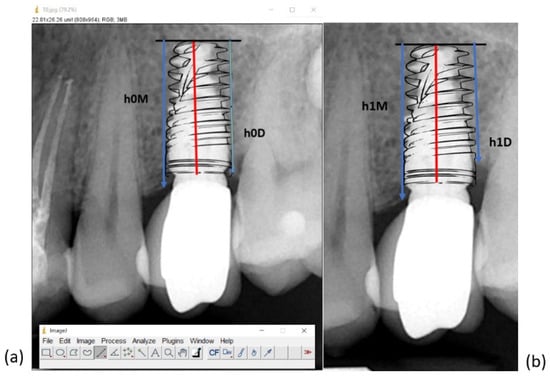

2.5. Peri-Implant Marginal Bone Loss

| mm | Group 1 | |||||||

|---|---|---|---|---|---|---|---|---|

| 1 | 2 | 3 | 4 | 5 | 6 | 7 | Mean (±SD) | |

| Mean MBL (±SD) | 0.07 (±0.01) | 0.07 (±0.04) | 0.08 (±0.01) | 1.0 (±0.17) | 0.05 (±0.02) | 0.02 (±0.01) | 0.85 (±0.09) | 0.32 (±0.45) |